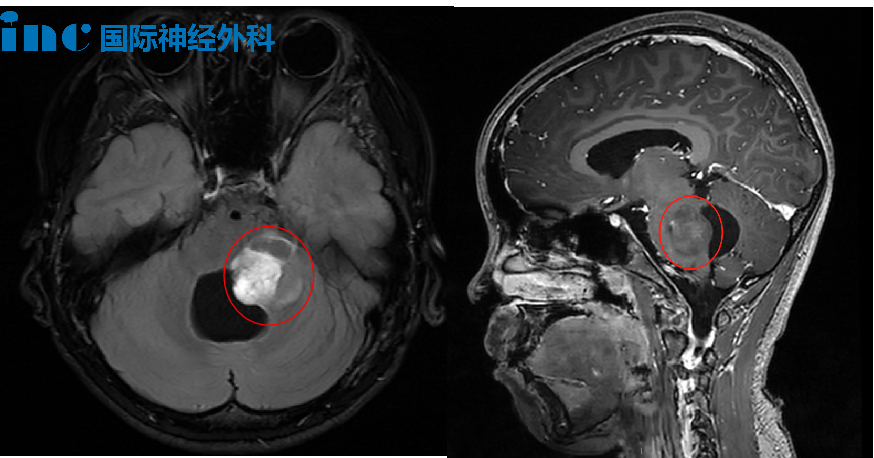

7岁女孩,中脑-丘脑胶质瘤,术后不久她就回归校园

7岁女孩秋秋偶然的头晕,竟是胶质瘤作祟。胶质瘤盘踞在脑干中脑脚部,延伸至右侧下丘脑,并向上延伸至丘脑。手术风险极大、安全切除极难——令无数医生不敢贸然接手。如此高难度手术,却是巴教授早已熟知的“日常”。在2025年巴教授中国行期间,他成功为秋秋安全切除肿瘤!如今的她早已回归校园,过去的苦难也在慢慢消散。点击阅读:小小头晕竟是中脑-丘脑胶质瘤作恶,术后不久她就回归校园!